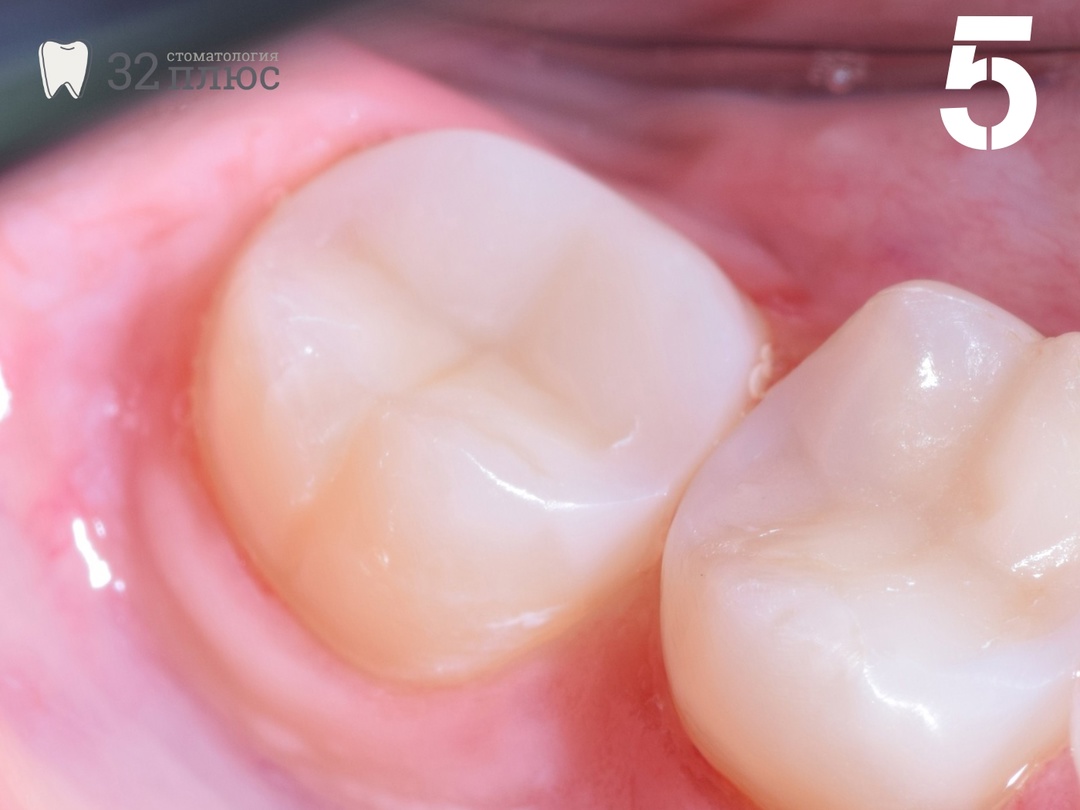

Зуб был восстановлен материалом Harmonize (Kerr) с сохранением нерва. Теперь пациентка может полноценно жевать этим зубом (фотография 5).